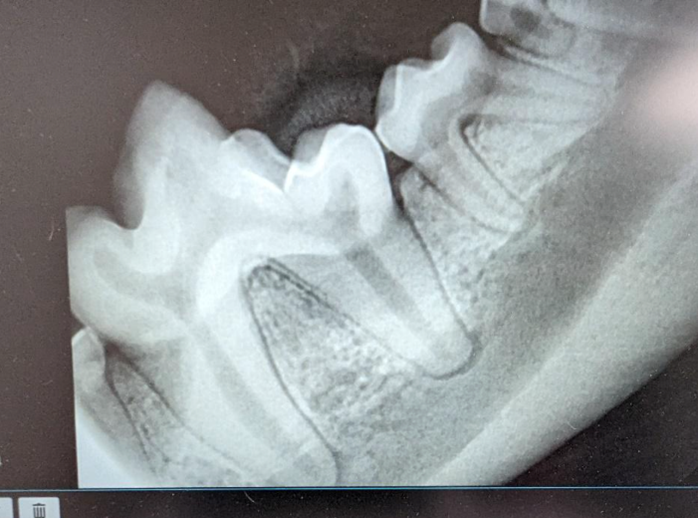

Dental X-ray:

Full mouth x-rays are taken of the tooth roots to evaluate for disease.

Once the teeth are clean and the x-rays are ready for review, the veterinarian will perform a full oral exam. A thorough dental exam involves a visual inspection of the oral cavity, probing for periodontal pockets and checking every tooth. A dental chart is used to describe any significant changes or problems. The teeth are assessed for abnormal color, enamel defects, large pockets in the gum around the tooth, bone loss, mobility, and other problems. The x-rays are also evaluated, and the veterinarian puts together the results of these test to determine if additional treatments are necessary. Dental extractions will then be performed if needed. Oral surgery in a pet is a complex thing and take extra time. The veterinarian may have to do a gingival flap in order to get to the roots that need to be extracted. You pet will also receive local anesthesia (aka a block) prior to any extractions, like you as a human would at the dentist.